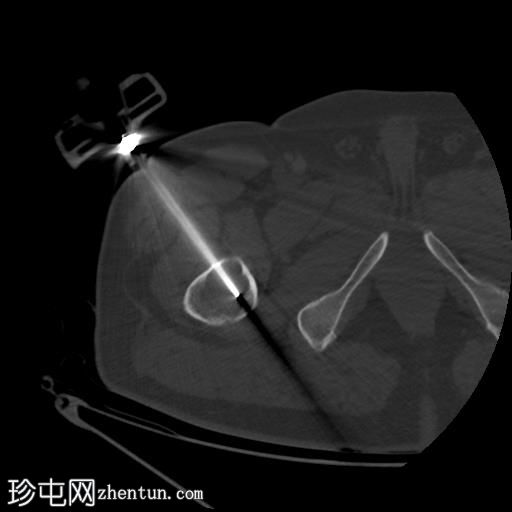

轴位

平扫

行CT引导下病变穿刺活检,术中及术后均未见并发症。

将活检针置于右股骨近端干骺端溶骨性透亮肿块中心后,从囊性病变中抽取血液。穿刺活检结果为阴性,未见骨髓浸润。因此,囊性病变的血液样本被送检进行组织病理学检查,结果显示无恶性肿瘤